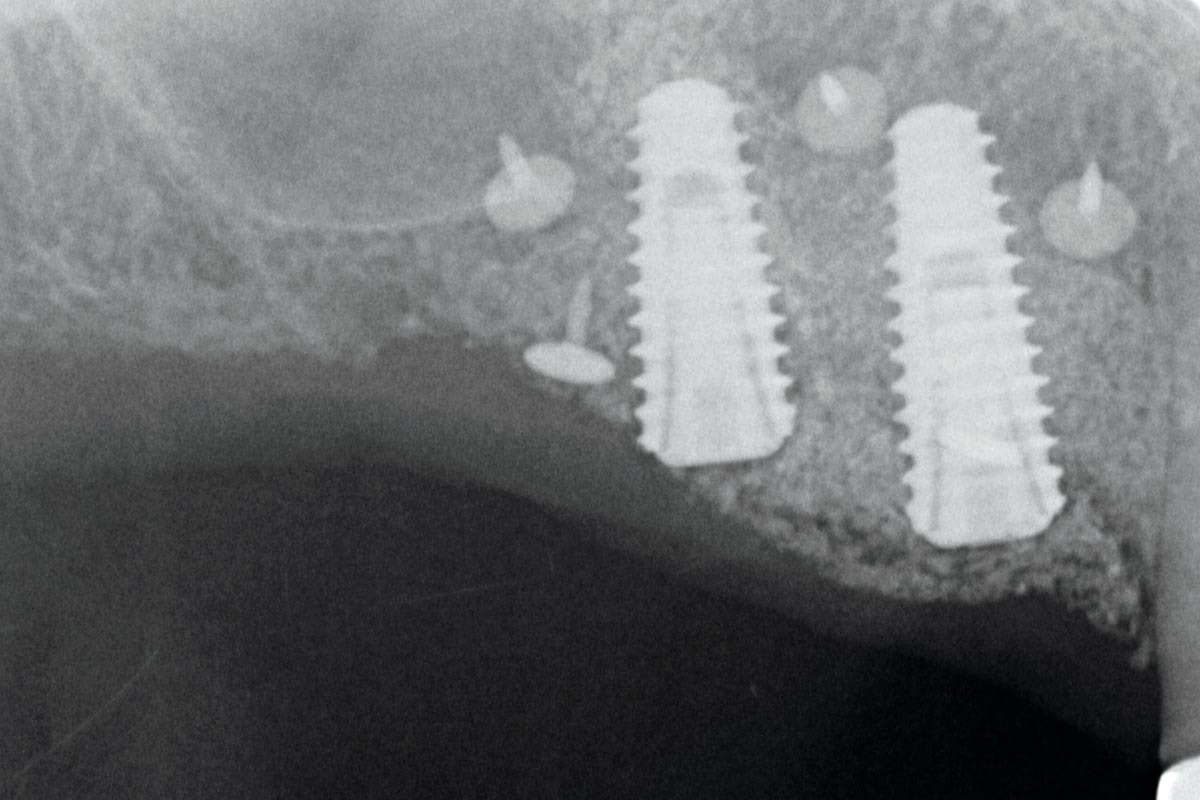

GBR with Jason membrane and cerabone

Dr. Filippo Fontana – Italy